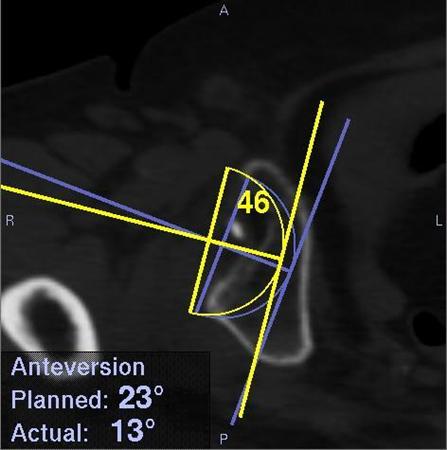

• ナビゲーションシステムのモニター画面の一部。実際に人工関節を挿入した角度と位置、当初の計画値も表示されるため、ずれの程度が分かる

開発されたナビゲーションシステムは、あらかじめ手術する関節部分をMRI(磁気共鳴画像装置)などで画像データを取っておき、それを基に3次元のCG画像を作って綿密な手術の計画を立てる。手術の際は赤外線照射で人工関節の位置や角度を測り、そのデータをCG画像に重ねて表示するため、計画通りの正確さで手術できる。